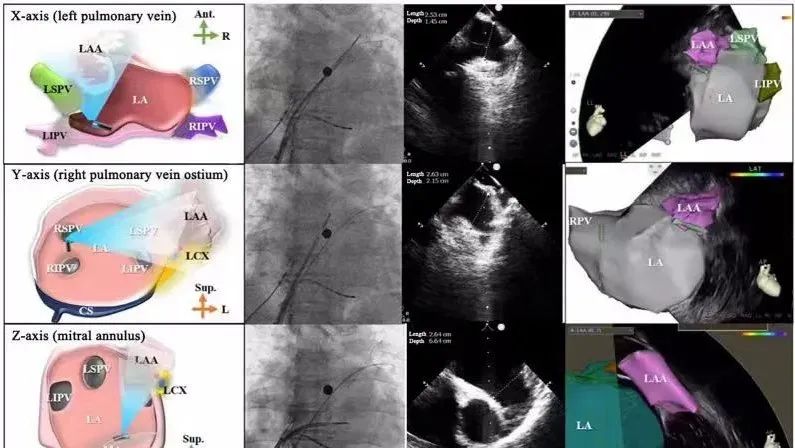

一種與心導(dǎo)管檢查相結(jié)合的超聲心動(dòng)圖診斷新興技術(shù),通過將超聲探頭置于心腔內(nèi)部,發(fā)射并接收超聲信號(hào),來(lái)精確獲取心臟解剖結(jié)構(gòu)、心臟血流動(dòng)力學(xué)等信息的實(shí)時(shí)成像。與其他影像技術(shù)相比,ICE技術(shù)具有操作簡(jiǎn)單、無(wú)輻射、安全性高、手術(shù)效率高、實(shí)用等優(yōu)勢(shì),ICE在很大程度上有望取代經(jīng)食道超聲心動(dòng)圖(TEE),成為電生理和結(jié)構(gòu)性心臟病領(lǐng)域的理想成像方式。

目前ICE技術(shù)已被應(yīng)用于左心耳封堵、房顫射頻消融、二尖瓣成形、房間隔缺損封堵等多種心臟介入手術(shù),應(yīng)用場(chǎng)景主要圍繞臟電生理、結(jié)構(gòu)性心臟病等領(lǐng)域,目前以電生理應(yīng)用為主。數(shù)據(jù)顯示,我國(guó)結(jié)構(gòu)性心臟病介入器械市場(chǎng)規(guī)模已從2017年的4億元增長(zhǎng)至2021年的20億元,年復(fù)合增長(zhǎng)率達(dá)48.3%;預(yù)計(jì)到2025年,該市場(chǎng)規(guī)模將達(dá)到104億元,可以預(yù)見ICE市場(chǎng)規(guī)模也將同步高速增長(zhǎng),未來(lái)市場(chǎng)發(fā)展空間廣闊。

心腔內(nèi)超聲(ICE)技術(shù)壁壘極高,國(guó)內(nèi)主要廠商核心部件仍舊為進(jìn)口,集成了超聲和圖像處理最前端技術(shù),包括超聲探頭、線纜、軟件成像算法等,是當(dāng)前內(nèi)窺超聲方向最具挑戰(zhàn)的領(lǐng)域。ICE的應(yīng)用經(jīng)歷了2D平面成像、3D三維立體成像、以及4D的實(shí)時(shí)三維立體成像階段。